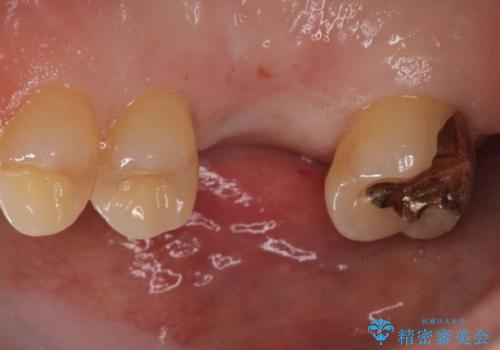

右上奥歯を抜歯された状態でした。

インプラントを埋入する際に骨の高さが不足していたので、骨造成も同時に行う計画としました。